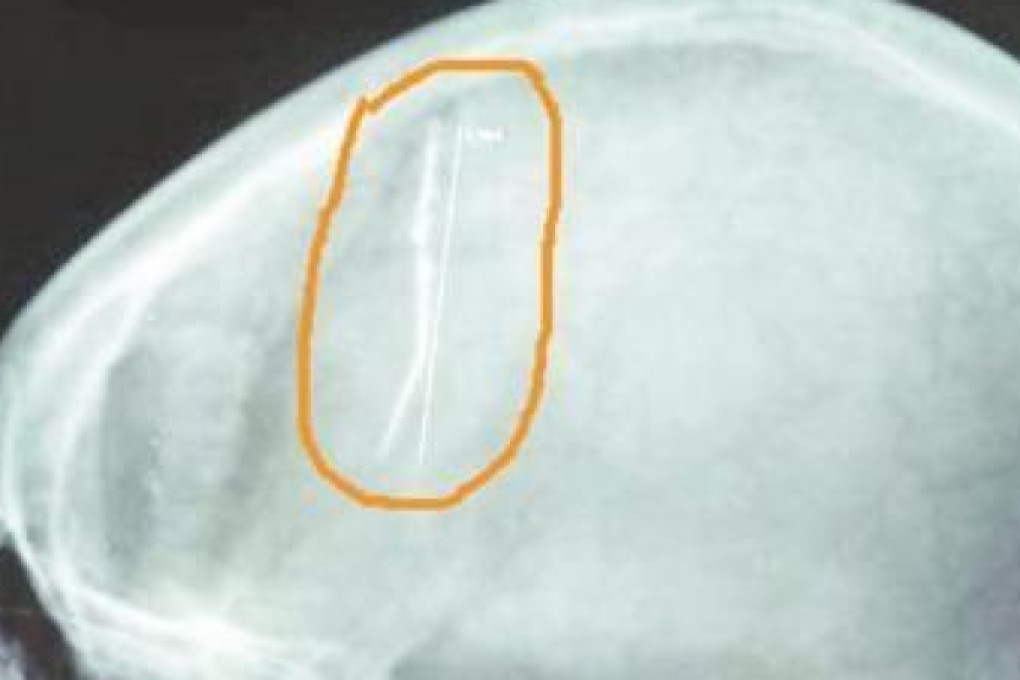

Doctors in a hospital in Luoyang, Henan province, have removed a 6cm-long rusty needle from the head of a 58-year-old woman, Dahe Daily reports.

The needle is thought to have been lodged in Wang Xiaohong’s brain since she was a child and has caused her headaches over the decades.

She also suffered epilepsy three decades ago, and didn’t know about the needle in her head until she had an X-ray after another epileptic fit recently.